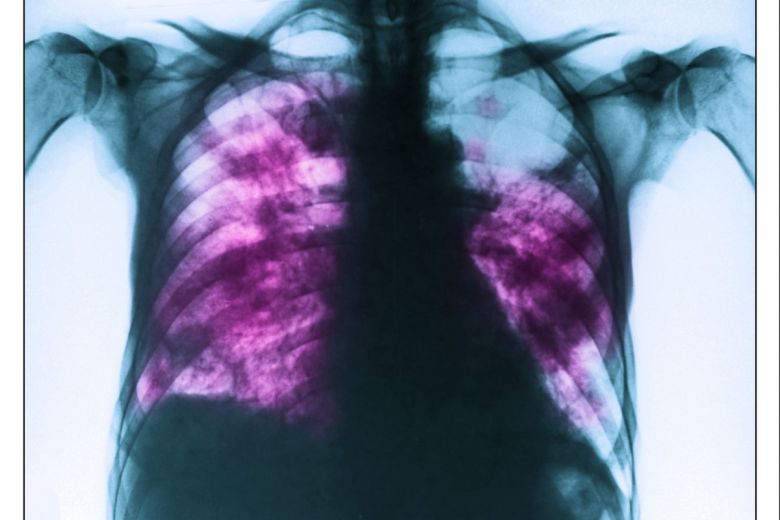

환자는 기존에 복용 중이던 약물이 없었으며, 피부보다는 눈, 입, 생식기 등 점막 중심의 증상이 두드러졌던 점이 주요 단서였다. 의료진은 혈액 검사 및 흉부 X선 검사를 통해 MIRM으로 최종 진단을 내렸다.